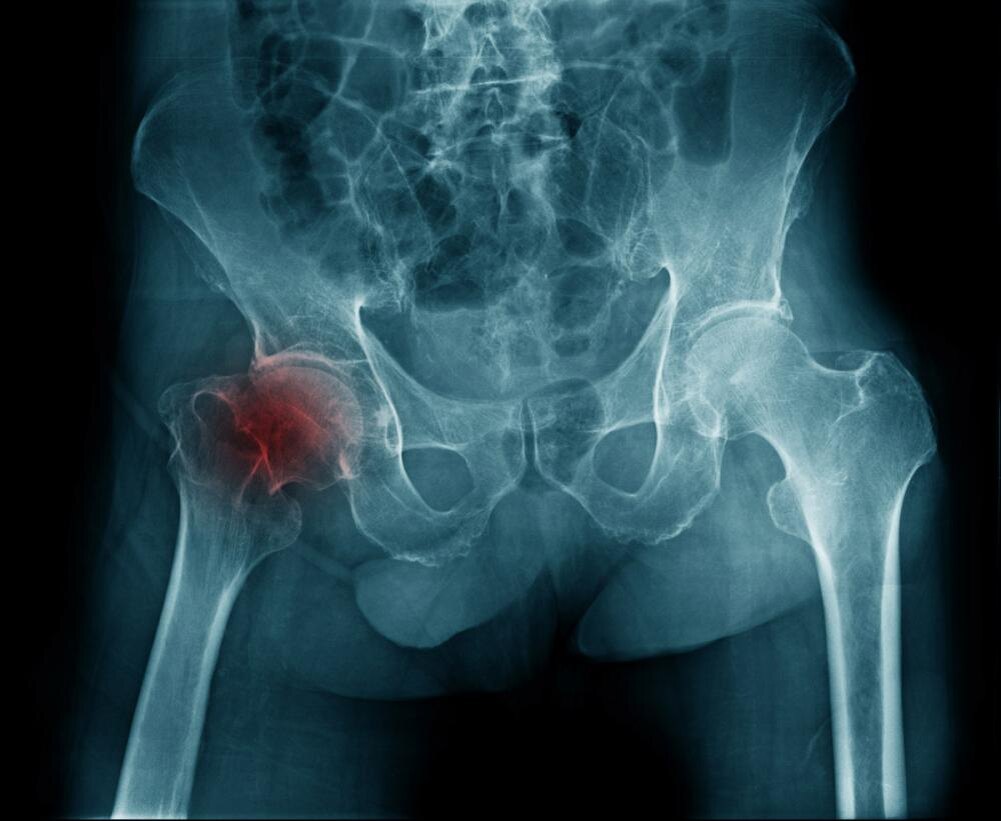

Коксартроз — это дегенеративно-дистрофическое заболевание тазобедренного сустава, при котором разрушается хрящ, покрывающий головку бедренной кости и вертлужную впадину. Без этого "буфера" кости начинают тереться друг о друга, вызывая боль, воспаление и постепенную деформацию сустава.

Когда хрящ разрушается, кости начинают соприкасаться напрямую. Организм пытается компенсировать это, образуя костные наросты (остеофиты) — но это только усугубляет ситуацию. Сустав деформируется, подвижность уменьшается, боль становится постоянной.

• На рентгене: почти ничего не видно или небольшое сужение суставной щели.

• На рентгене: сужение суставной щели на 30–50%, костные наросты.

• На рентгене: сужение суставной щели более чем на 50%, выраженные остеофиты, изменение формы костей.

• На рентгене: полное отсутствие суставной щели, выраженная деформация.

2. Рентген. Основной метод диагностики. Показывает степень разрушения хряща, наличие остеофитов.